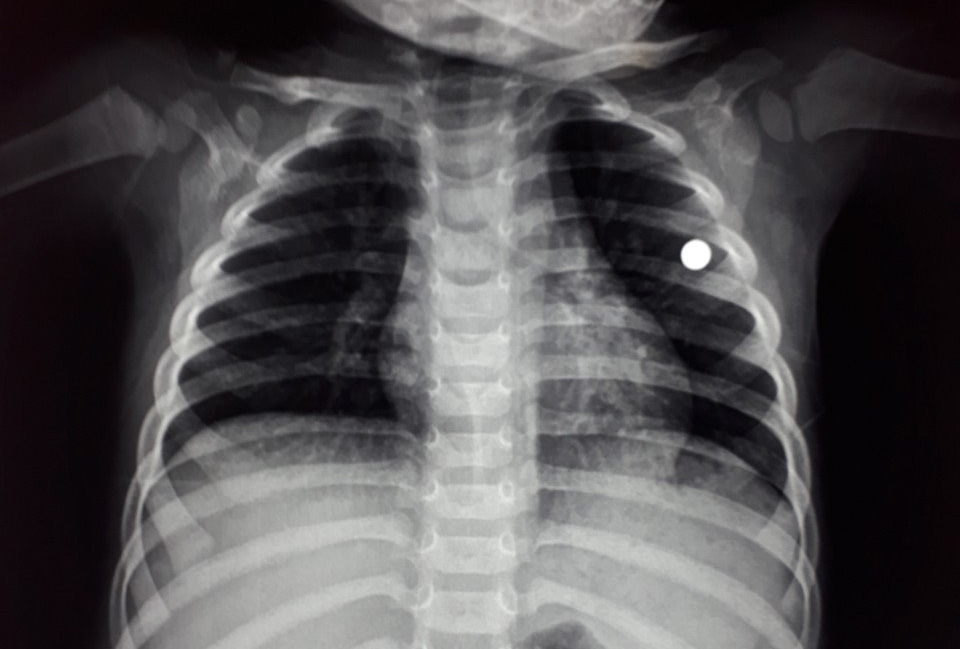

Viên đạn bi (dấu tròn màu trắng) nằm trong ngực trái cháu V. nhìn từ hình ảnh chụp X-quang - Ảnh do Bệnh viện Nhi Thanh Hóa cung cấp

Cháu V. nhập viện trong tình trạng có vết thương ở ngực trái, kích thước 1,5 x 1,5cm, gần tim, chảy máu, chưa gây tổn thương đến phổi. Các bác sĩ của khoa tim mạch - lồng ngực Bệnh viện Nhi Thanh Hóa đã phẫu thuật gắp viên đạn từ ngực trái cháu V. ra ngoài thành công.